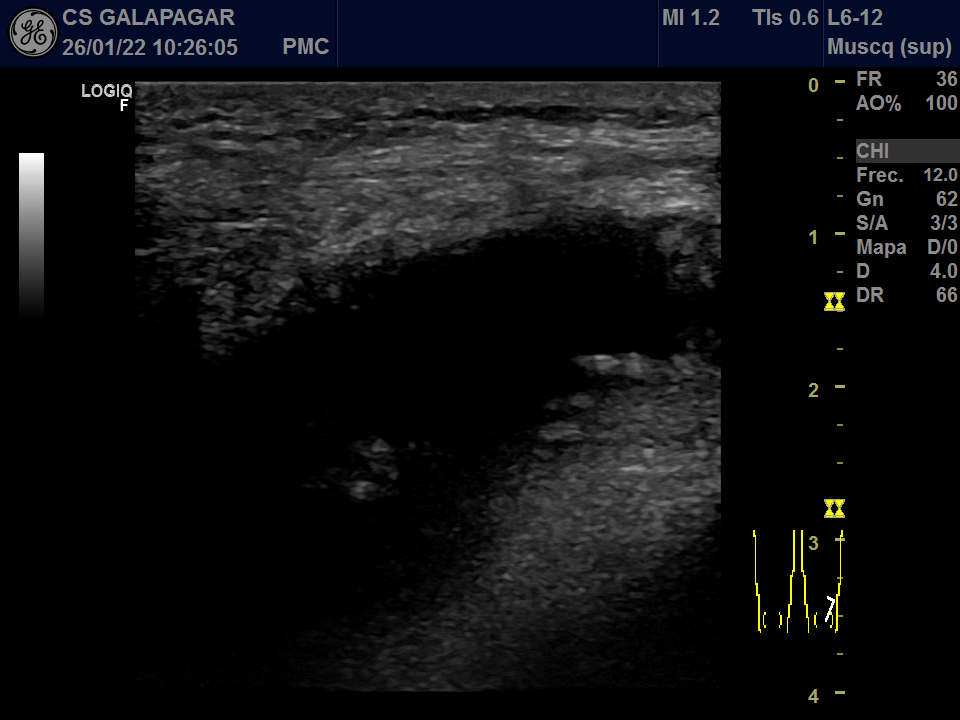

01/22: Abundante derrame en bursa con sinovitis muy proliferativa.